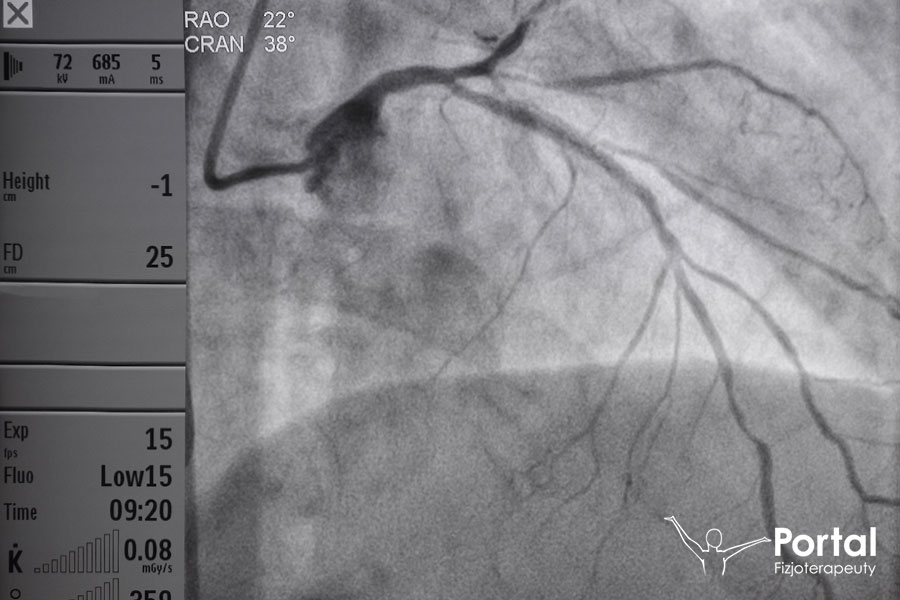

Angiografia to badanie polegające na uwidocznieniu obrazu naczyń krwionośnych przy pomocy wybranego promieniowania. Najczęściej jest to promieniowanie rentgenowskie, jednak równie